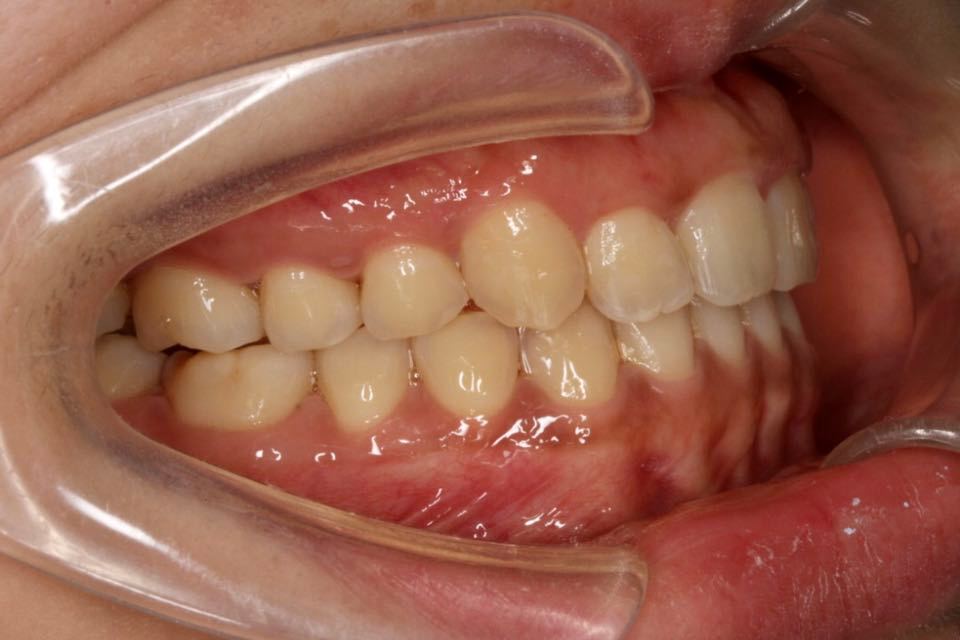

矫正前口内照:

口内:恒牙列,牙列拥挤(中度)。上下颌牙弓呈方圆型。左右对称。右侧磨牙近中性关系,左侧磨牙近中关系,右侧尖牙远中关系,左侧尖牙远牙中性关系。上颌中线偏右2mm,下中性居中。